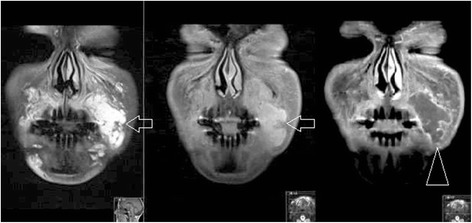

Fig. 5.

Delayed reaction to calcium hydroxyapetite, coronal MRI (T1FS, T2FS, T1FS with gadolinium). Note the filler in the left infraorbital triangle (open arrows), with the delayed reaction extending to the nasolabial sulcus, causing the gross asymetry

Fig. 6.

Acute allergic reaction to hyaluronic acid in the left nasolabial sulcus and mouth angle sulcus region (open arrows) on coronal MRI (T2FS, FS T1FS with gadolinium). This soft tissue reaction is often reffered to “cellulitis-like.” Note the normal filler in the right lower infraorbital triangle and nasolabial sulcus (arrowhead)